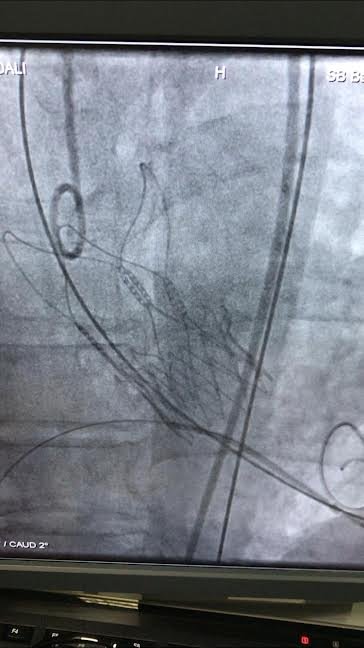

Atatürk Şehir Hastanesinde başarılı tıbbi işlemlere bir yenisi daha eklendi. Kalp krizi ile başvuran 77 yaşındaki G.D isimli bayan hastanın yapılan tetkikleri sonucunda aort kapağı ileri derecede daralmış olduğu tespit edildi. Kardiyoloji Bölümünden Doç. Dr. Erkan AYHAN ve ekibi tarafından uygulanan bu yöntem sayesinde hastanın göğüs kafesi açılmadan kasık damarları yoluyla kireçli aort kapağı yeni bir protez kapakla değiştirildi.

“Hastamız ciddi aort kapak darlığı nedeni semptomatik ve tedavi olması gereken bir hasta idi. Bu hastalığın altın standart tedavisi cerrahi olarak kapağın değiştirilmesidir. Ancak ileri yaşı olan veya eşlik eden diğer sebepleri nedeni ile cerrahisi çok riskli olacak hastalarda TAVİ olarak isimlendirdiğimiz yöntemle kasık damarından girilerek yeni bir biyoprotez kapak takıyoruz. Kardiyoloji branşını ilgilendiren hizmetlerimizi başta İl Sağlık Müdürümüz Sayın Dr. Serkan Kadir Keskin olmak üzere sağlık müdürlüğü yetkililerimiz ve Sayın Başhekimimizin destekleri ve bizlerin gayretleri ile yürütmekteyiz. Hastamızın tedavisine vesile olmaktan ise büyük mutluluk duymaktayız.”